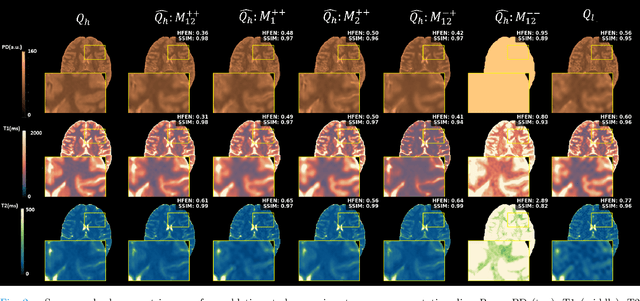

Abstract:Quantitative MRI (qMRI) offers significant advantages over weighted images by providing objective parameters related to tissue properties. Deep learning-based methods have demonstrated effectiveness in estimating quantitative maps from series of weighted images. In this study, we present qMRI Diffusor, a novel approach to qMRI utilising deep generative models. Specifically, we implemented denoising diffusion probabilistic models (DDPM) for T1 quantification in the brain, framing the estimation of quantitative maps as a conditional generation task. The proposed method is compared with the residual neural network (ResNet) and the recurrent inference machine (RIM) on both phantom and in vivo data. The results indicate that our method achieves improved accuracy and precision in parameter estimation, along with superior visual performance. Moreover, our method inherently incorporates stochasticity, enabling straightforward quantification of uncertainty. Hence, the proposed method holds significant promise for quantitative MR mapping.